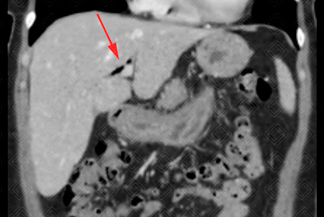

Texto alternativo para a imagem Figuras 1, 2, 3 e 4. Créditos: Dra. Elazir Mota - Rio de Janeiro/RJ.

Descrição das figuras 1, 2, 3 e 4: Tomografia computadorizada do abdome. Estudo pós-contraste (fase portal), cortes axiais e coronais evidenciando a presença de gás (setas vermelhas) no interior do colédoco e via biliar intra-hepática esquerda. Após colher nova história com a paciente, havia relato de procedimento recente (colangiopancreatografia retrógrada endoscópica [CPRE]).

Aerobilia: Também chamada de pneumobilia. Trata-se da presença de gás no interior da árvore biliar. As principais etiologias são abordagem recente das vias biliares (CPRE, colangiografia intra-operatória), incompetência do esfíncter de Oddi (congênita, uso de atropina, esfincterotomia e pancreatite crônica), fístula bilioentérica, processos infecciosos (colangite, colecistite enfisematosa, abscesso hepático e ruptura de cisto hidático).